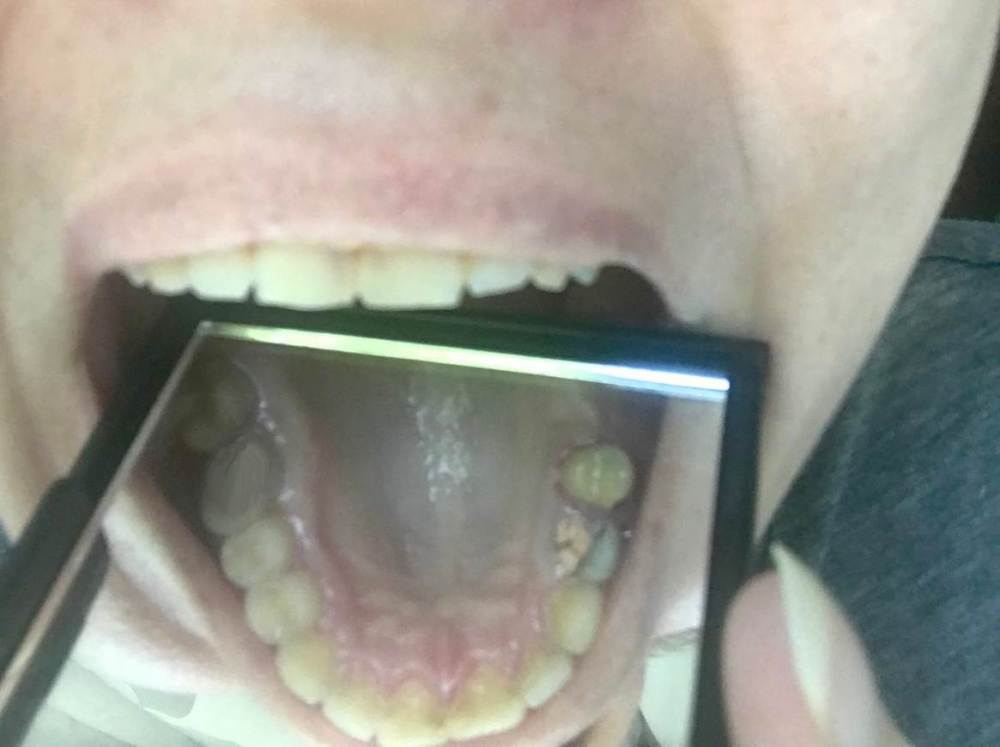

Sunrise129 Опубликовано 22 сентября, 2021 Поделиться Опубликовано 22 сентября, 2021 (изменено) Здравствуйте. Уже не знаю, куда обращаться. Почти полгода назад ощутила жжение слизистой рта. Сначала не сильно беспокоило, в области ретромолярного треугольника, лечила как стоматит, поласкала, ничего не помогло. Обратилась к стоматологу, затем пародонтологу - результата ноль, никакие полоскания и антисептики не помогают. Тем более, что они особо "ничего такого" там не видели. В итоге на сегодня рот печет, язык сухой, воспаленный и имеет белый цвет. Болит нёбо, практически возле каждого зуба воспаленная лунка красная. Больно кушать, больно даже разговаривать. Там, где раньше пекли десна, теперь стали кровоточить с гнойным экссудатом. Обошла 5 пародонтологов - все предлагают только чистку, насчет слизистой ничего сказать не могут и отмахиваются, мол, ничего там нет, дисбиоз. Есть проблемы с гландами, в первом посеве был стрептококк 10х8, но это было написано в пределах нормы, промыли чем-то в поликлинике, не антибиотиком, потому что "показаний нет". Во втором посеве был золотистый стафилококк 10х4. Все говорят, что это "ничего страшного". Между тем уже в августе он был 10х5 степени.... Но лор не прописывает антибиотиков, только полоскания, которые до одного места. Анализы на инфекции (самые страшные в том числе и ЗППП) отриц. На кандиду уже 4 раза сдавала - отриц. Была у гастроэнтеролога, делала гастроскопию - все нормально. Была уже у инфекциониста (тот прописал на всякий случай от всего антибиотики, противовирусные, и еще что-то, но я не стала так рисковать), лора, дерматовенеролога, 5 пародонтологов - результат нулевой. Еще в доме есть длинношерстный кот, но аллергии никогда у меня не было. Если кто сталкивался с подобным или знает толкового врача - подскажите, пожалуйста. Буду очень благодарна. Изменено 22 сентября, 2021 пользователем Sunrise129 Ссылка на комментарий